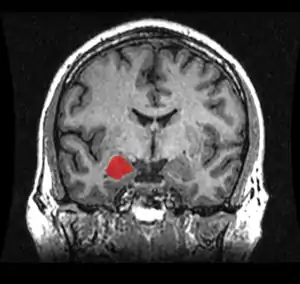

Amygdala

The amygdala is an almond-shaped cell mass, located in the temporal cortex. It is made up of different groups of cells, called the lateral, basal and accessory basal nuclei – collectively called the basolateral amygdala. Structures surrounding the basolateral amygdala, including the central, medial and cortical nuclei are traditionally called the ‘amydaloid complex’, and together with the basolateral amygdala are collectively called ‘the amygdala’ (Davis & Whalen, 2000). The amygdala is associated with fear and emotional significance of a stimulus (Burton, Westen, Kowalski, & Westen, 2015). Stimulation of the amygdala is associated with autonomic reactions such as the ‘fight or flight’ response, increasing heart rate and blood pressure (Thomas, 2001). A study into lesions of the amygdaloid complex of monkeys in 1956 showed that the lesions on the amygdala diminished the monkey’s normal fear response (Weiskrantz, 1956). Studies indicate that increased amygdala volume may be correlated with increased amygdala reactivity (Cohodes & Gee, 2017). Studies have found that children and adolescents with anxiety related disorders show larger amygdala volumes (Milham & Banich, 2005), and another study in 2010 by Tottenham et al., found that increased amygdala volume predicted symptoms of anxiety in post-institutionalised children. Another study showed that children with anxiety disorders showed exaggerated amygdala responses to fearful faces compared to healthy children, suggesting that the amygdala function is affected by anxiety related disorders (Thomas, 2001).